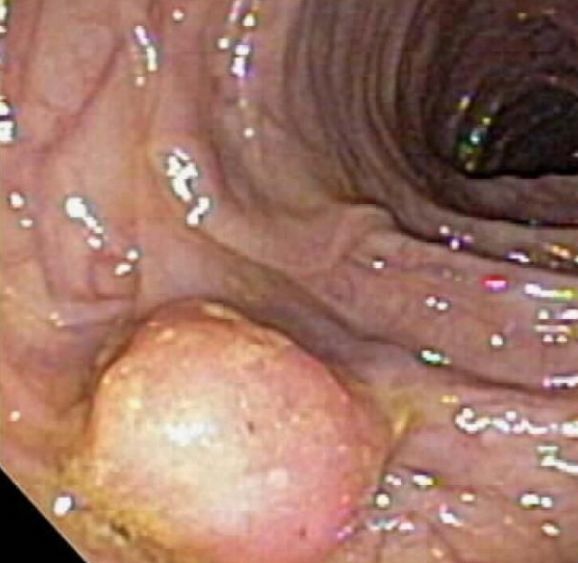

Premalignant neoplasm seen on colonoscopy

Prerequisites for effective cancer screening tests

There must be (1) a well-characterized and identifiable precursor lesion, and (2) enough lead time that it can be removed before it becomes invasive.

The best examples are the colonoscopy and pap smear cytology